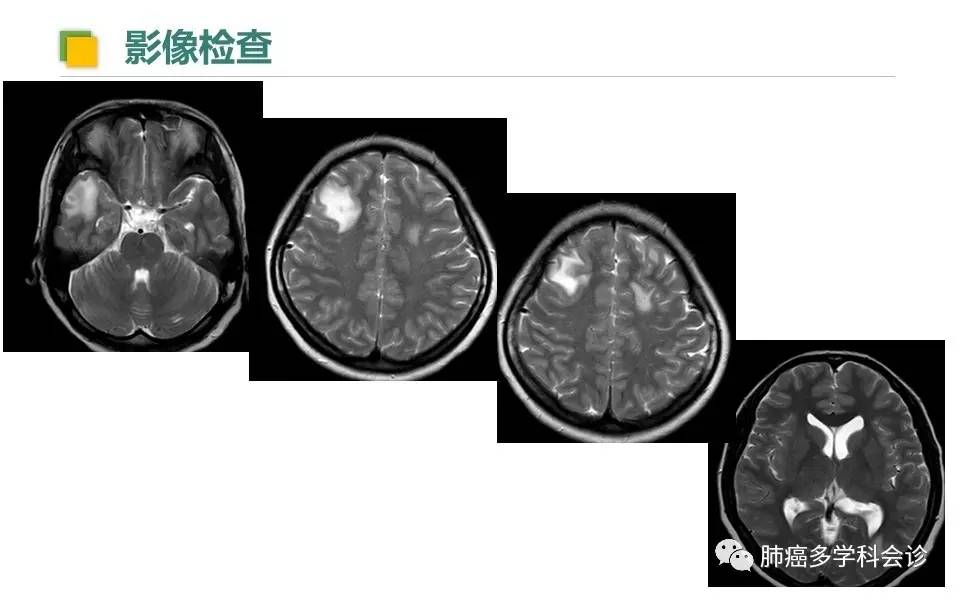

绝处逢生:NGS助力肺癌精准医疗--记1位ROS-1阳性者